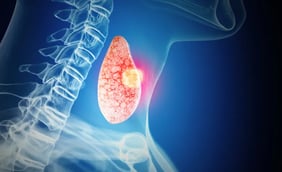

Thyroid Cancer

Thyroid cancer is a type of cancer that starts in your thyroid gland. A gland is an organ in your body that makes a substance.